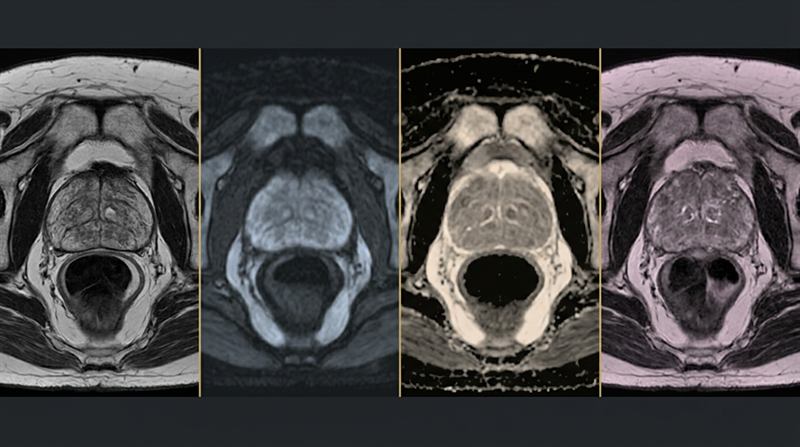

Dr Raji Kooner successfully completed the first pure single port robotic procedure in NSW — a true single-incision approach without any assisting ports — with support from Dr Ryan Nelson (USA).